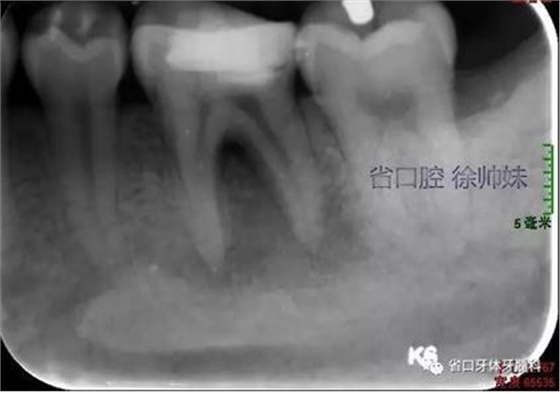

根尖片(圖2)示36大面積充填物近髓,根尖周及根分叉大面積低密度影。

圖2 術前根尖片